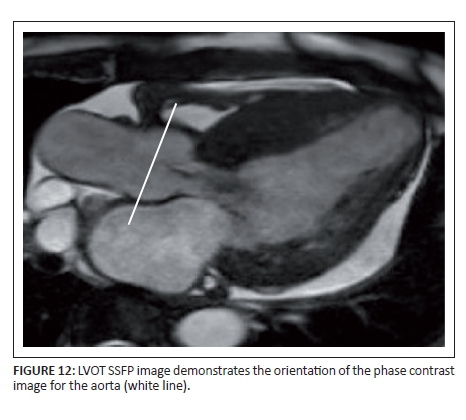

Phase contrast sequences are also used for valvular assessment, particularly of the aortic and pulmonary valves. These sequences are based on the accumulated phase of moving protons and are used to measure the peak velocity, stroke volume, and regurgitation fraction in a vessel. These images needs to be acquired directly perpendicular to the vessel for accurate measurements (Figure 12). Valvular stenosis is seen as increased signal in the region of the flow jet (Figure 13).